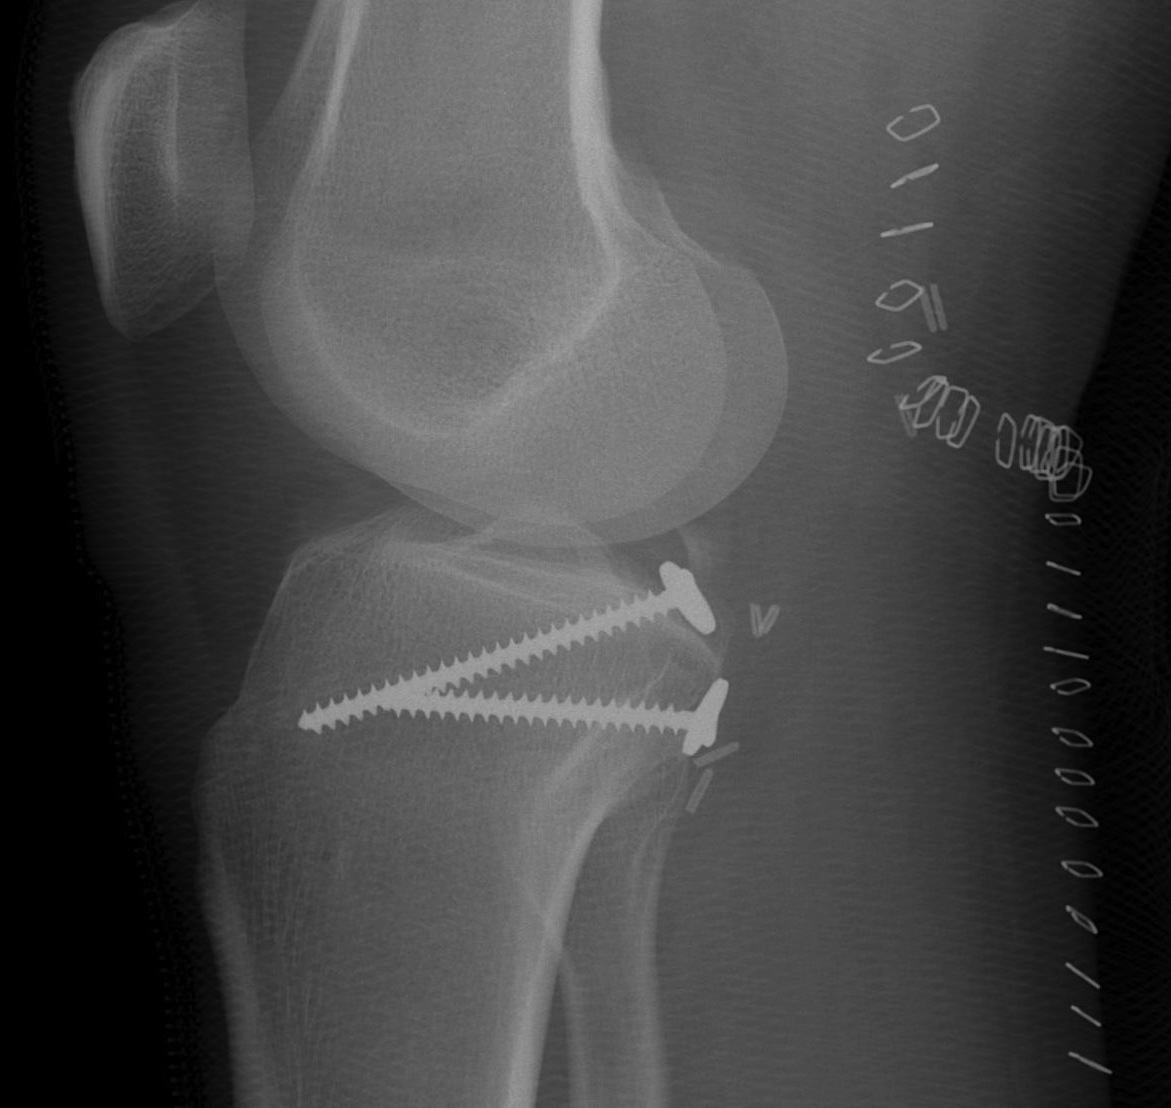

Fixation options

- size dependent

- screw / staple